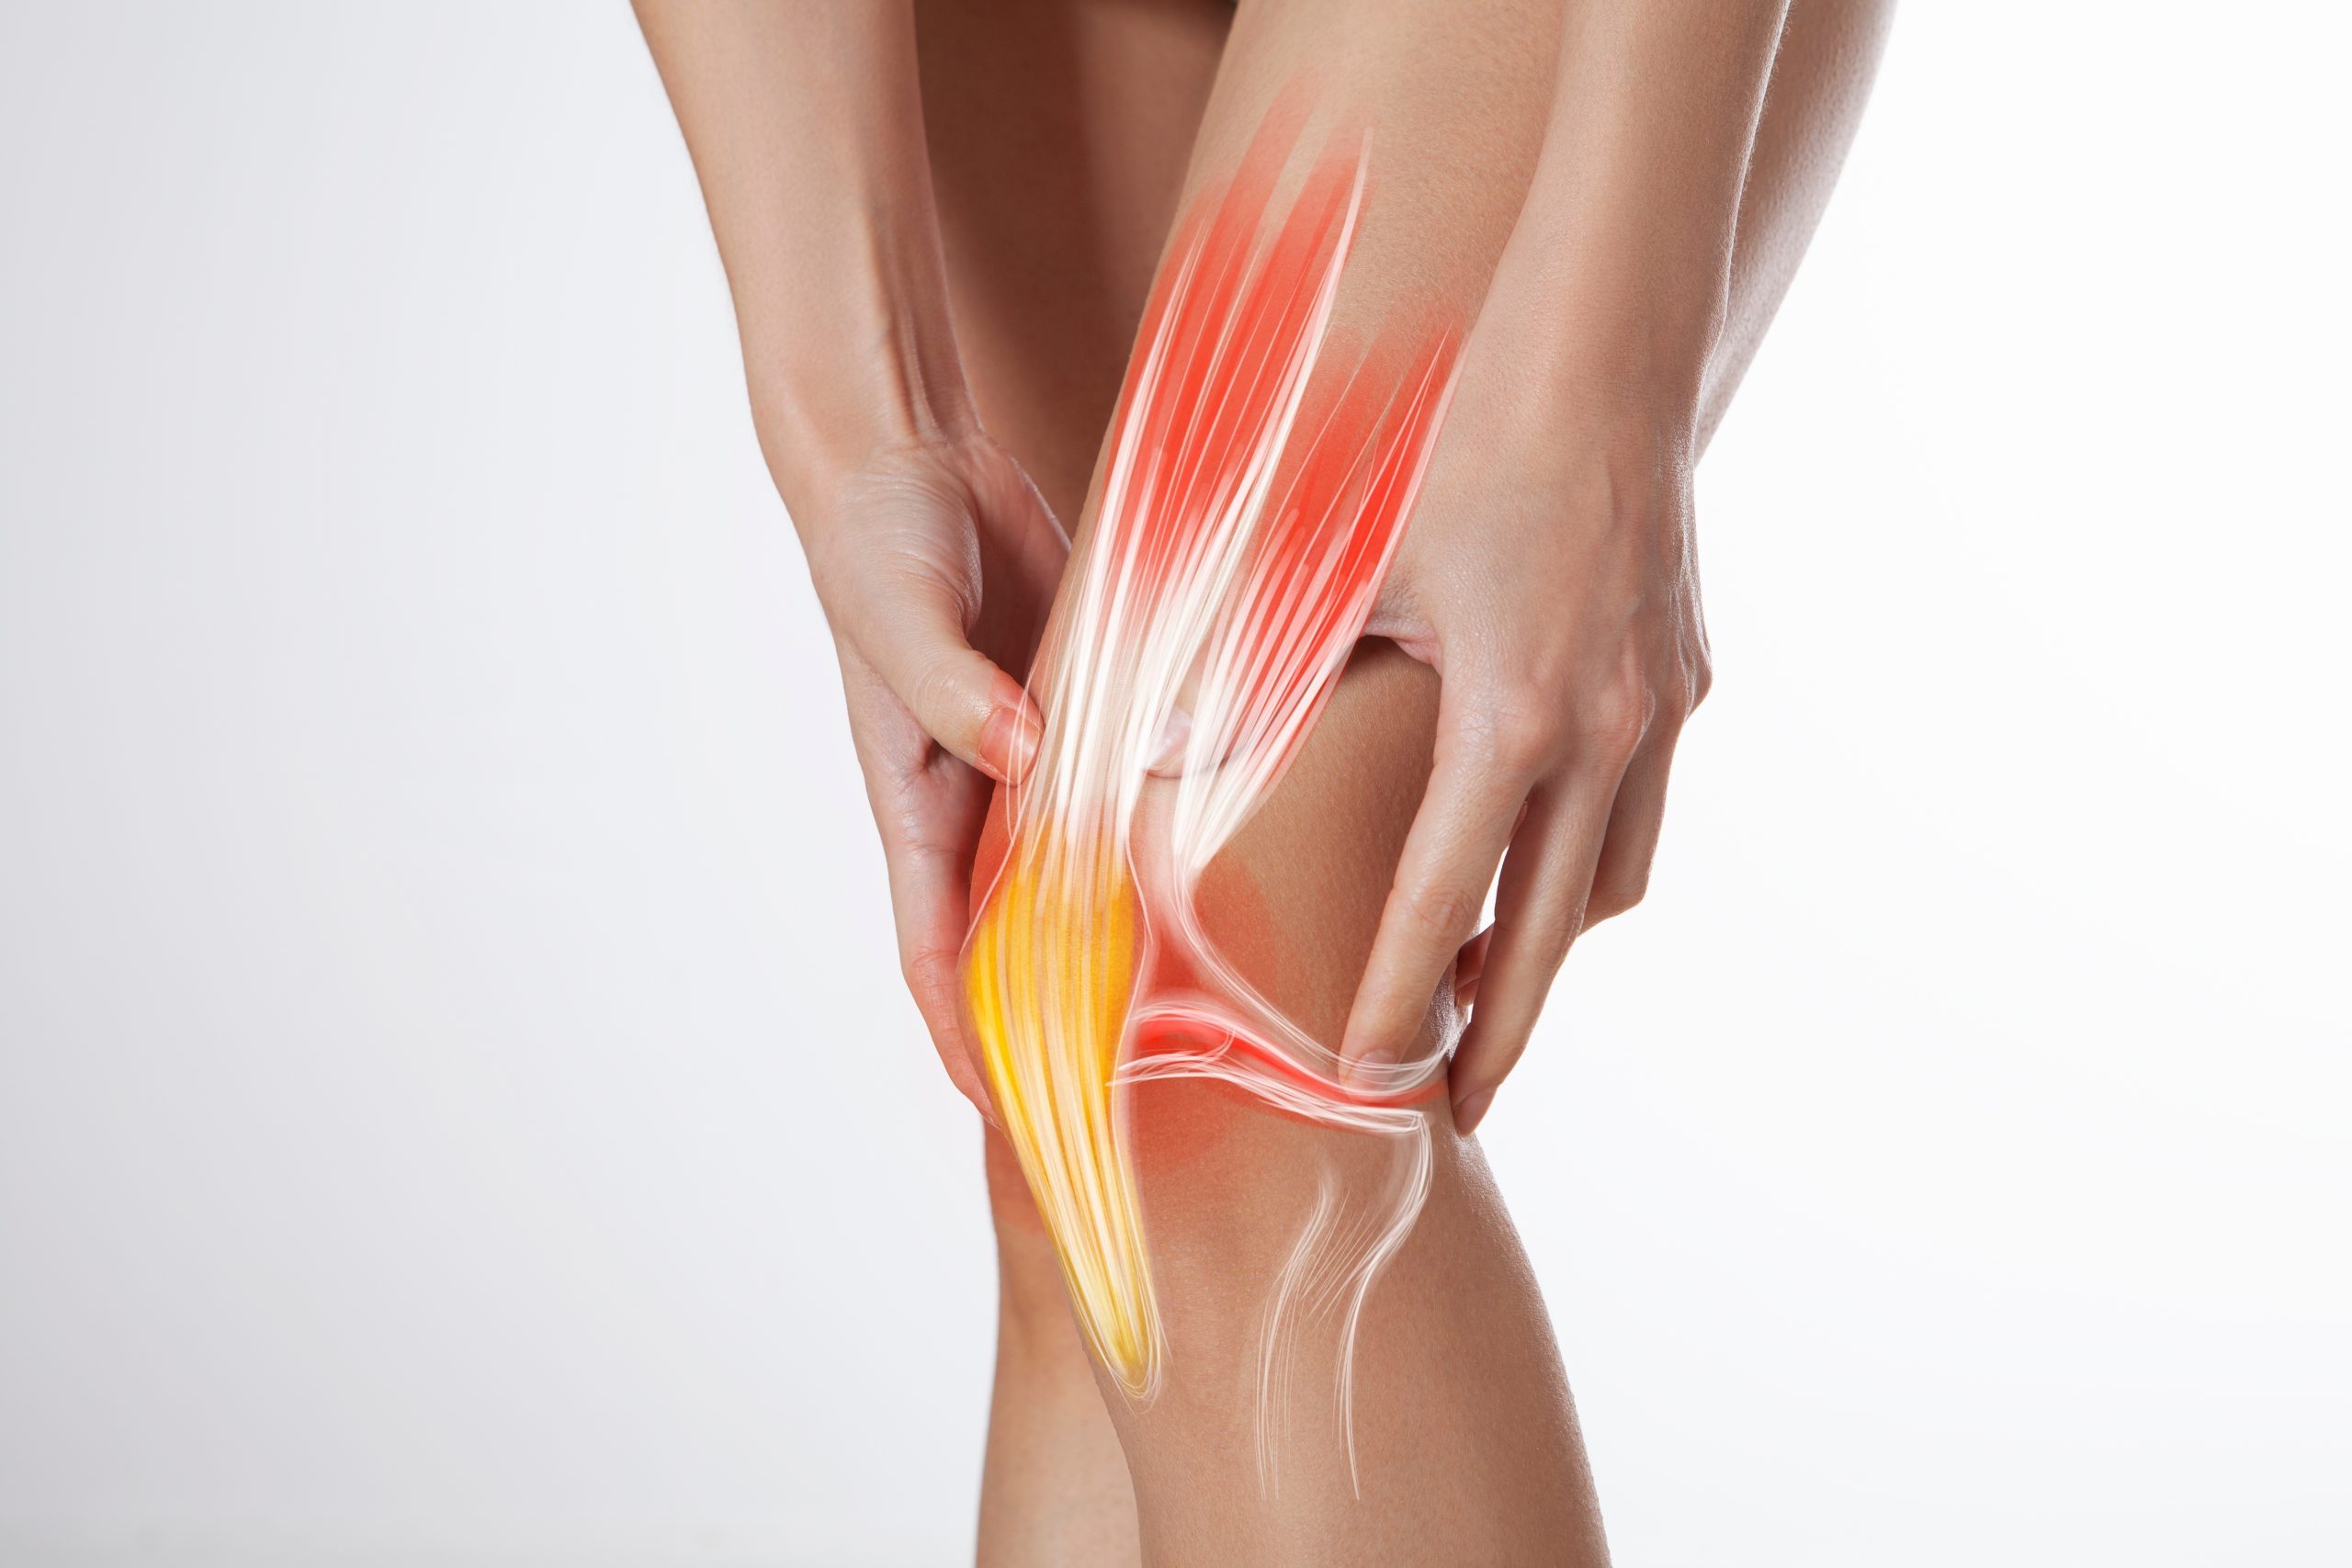

La rodilla es la articulación central de los miembros inferiores, una unión crucial entre el fémur y la tibia. En esta compleja estructura se encuentran huesos, ligamentos, tendones, meniscos y un conjunto de músculos que desempeñan un papel fundamental en la estabilidad y movilidad del cuerpo. Su función principal es sostener el peso del cuerpo cuando la persona está de pie, convirtiéndola en una de las articulaciones más importantes.

La rodilla es una articulación compleja y vital para nuestra movilidad diaria. Esta articulación es propensa a una variedad de padecimientos que van desde el dolor hasta el desgaste de la rodilla. Las lesiones en esta área pueden afectar significativamente tu calidad de vida, limitando tus actividades y causando dolor persistente.